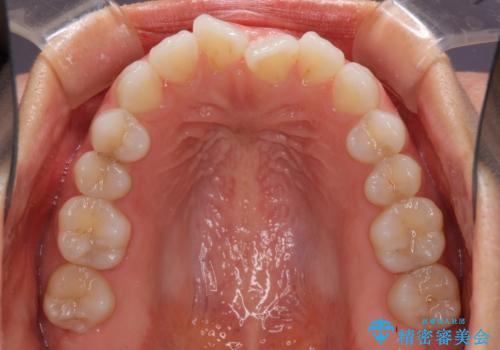

- 上下の前歯の反対咬合を気にして来院された患者様です。

インビザラインを用い、下顎はIPR(歯と歯の間を削る)と歯列全体を後方に移動させ、上顎は前歯を持ち上げることで、反対咬合を改善していくこととしました。

インビザラインによる反対咬合の改善は、上の歯が下の歯を乗り越えていく期間に咬み合わせが非常に不安定となり、治療が長期化することがあります。

こちらの患者様も、一時的に前歯でしか咬めない時期がありましたが、比較的早く咬み合わせが安定し、1年ほどで治療を終えることができました。